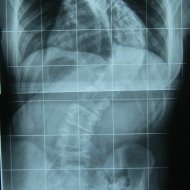

Farklı tipte skolyozu olan hastaların ameliyat öncesi ve sonrası fotoları: